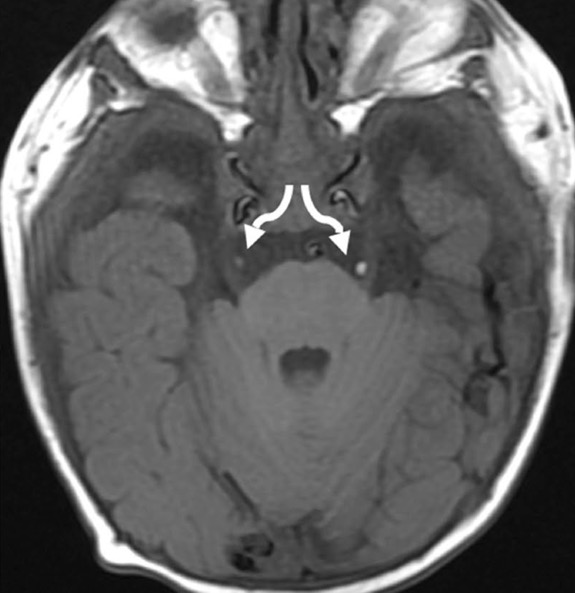

c. Lipomatose encéphalocraniocutanée (ECCL): peau, yeux, SNC)

ECCL: